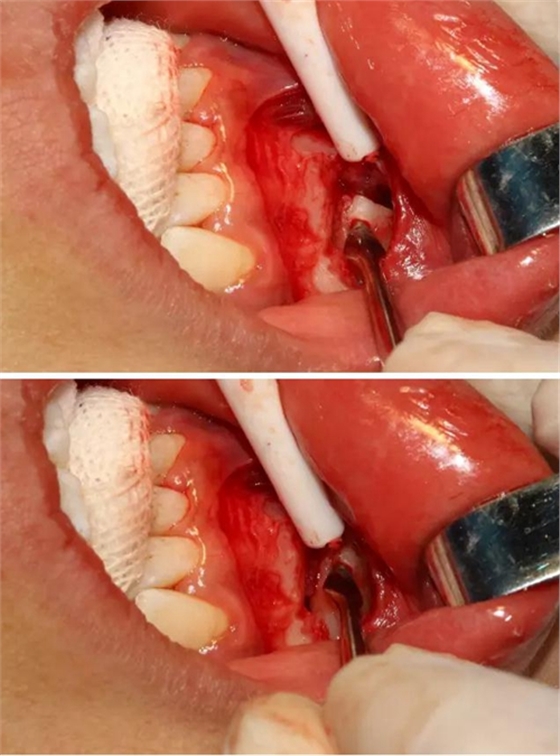

同時(shí)在剩余的根部斷面4MM下,預(yù)備2MM的溝槽,通過(guò)剝離子的三角尖端將牙體推出

三彎探針取出牙根部分

去除含牙囊壁